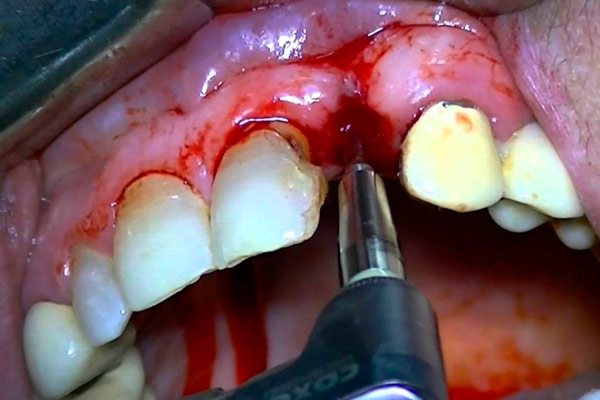

Сильное кровотечение

Во время имплантации зубов небольшое кровотечение считается нормой, и оно в большинстве случаев легко устраняется обычными гемостатическими техниками. Обильное же кровотечение может возникнуть как по вине врача, так и по вине самого пациента.

В силах каждого человека, садящегося в стоматологическое кресло, снизить риски развития данного осложнения. Чаще всего кровотечение из раны возникает при повышении артериального давления, а также при нарушении свертываемости крови (прием препаратов, «разжижающих кровь», сердечнососудистая патология и т.д.).

Контроль АД, своевременный прием препаратов под контролем кардиолога или терапевта, правильная медикаментозная и психотерапевтическая седативная (снимающая нервное напряжение) подготовка, а также обязательное информирование стоматолога-имплантолога об имеющихся заболеваниях позволит избежать не только ранних кровотечений во время имплантации, но и в отсроченный период. Немаловажное значение с целью профилактики осложнений имеет также выполнение всех рекомендаций после имплантации зубов, когда свежая рана является зоной повышенного внимания, особенно, если за один день было установлено более 4-5 зубных имплантантов.